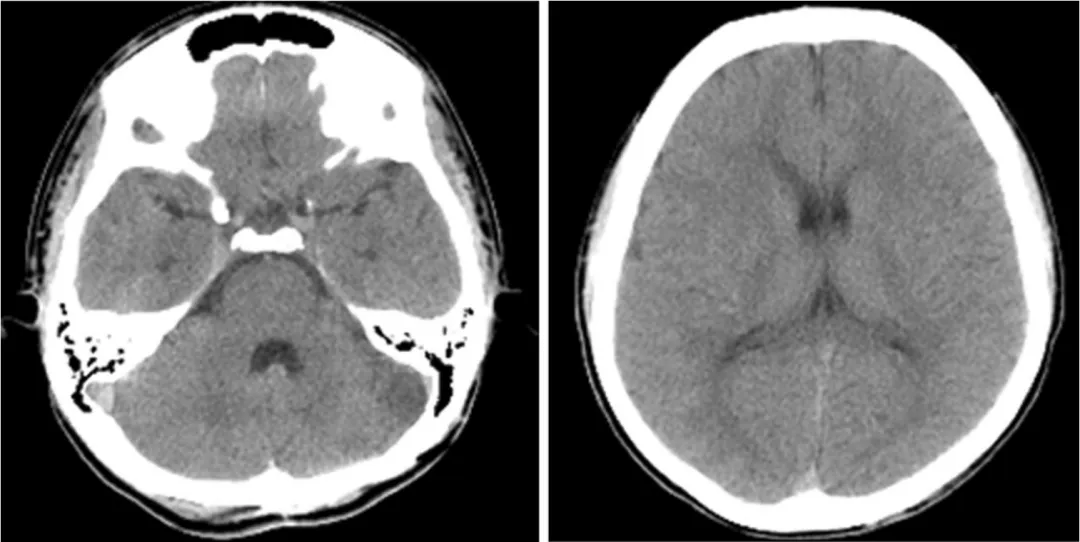

术后CT检查未见明显缺血性病变或脑积水

术后血管造影显示动脉瘤和动静脉瘘完全切除,无残留病灶